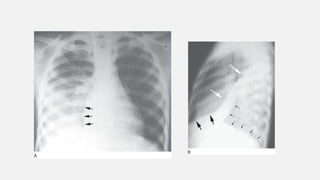

• #29 Peripheral subpleural (reverse bat-wing) consolidation. A: Chest radiograph in a patient with chronic eosinophilic pneumonia shows areas of consolidation in the subpleural lung. The perihilar regions are spared. B: CT in a patient with OP shows patchy areas of consolidation in the subpleural lung.

• #33 4. Diffuse air-space nodules in bronchopneumonia. Multiple small nodular opacities are typical of spread of infection through the airways. This represented a bacterial bronchopneumonia, but other organisms such as TB, MAC, fungus, or viruses may be involved.